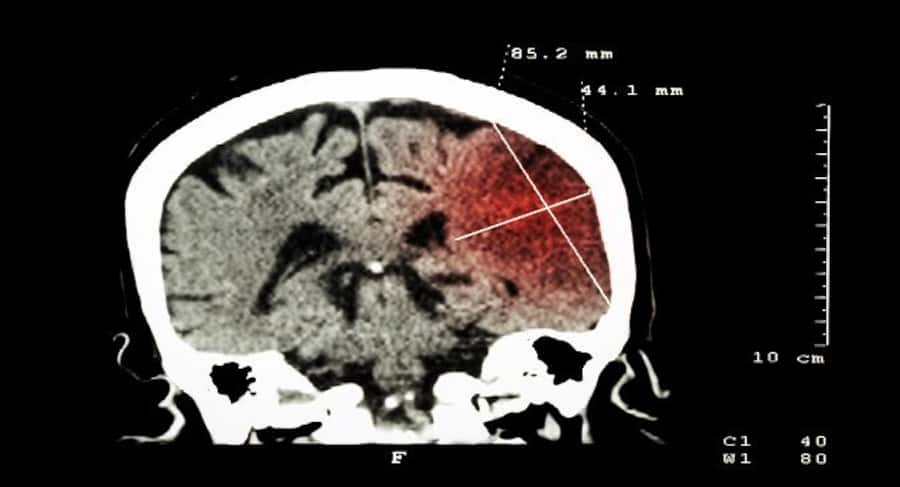

The relation between poor air quality and pulmonary disease such as asthma, COPD is well documented and understood. However, most people don t realize that breathing in the low-quality air can also cause a stroke.Stroke is a medical condition in which brain cells die due to the reduced blood supply. A stroke can be caused by blockage or rupture of the blood vessels supplying the brain. Dr Gaurav Thukral, COO HealthCare atHome says, Lack of awareness is a major cause. People are unaware of the linkage of stroke with air pollution and often do not take the necessary steps to avoid it. Even after stroke attacks, people underestimate the importance of rehabilitation, which can be the key to complete recovery.